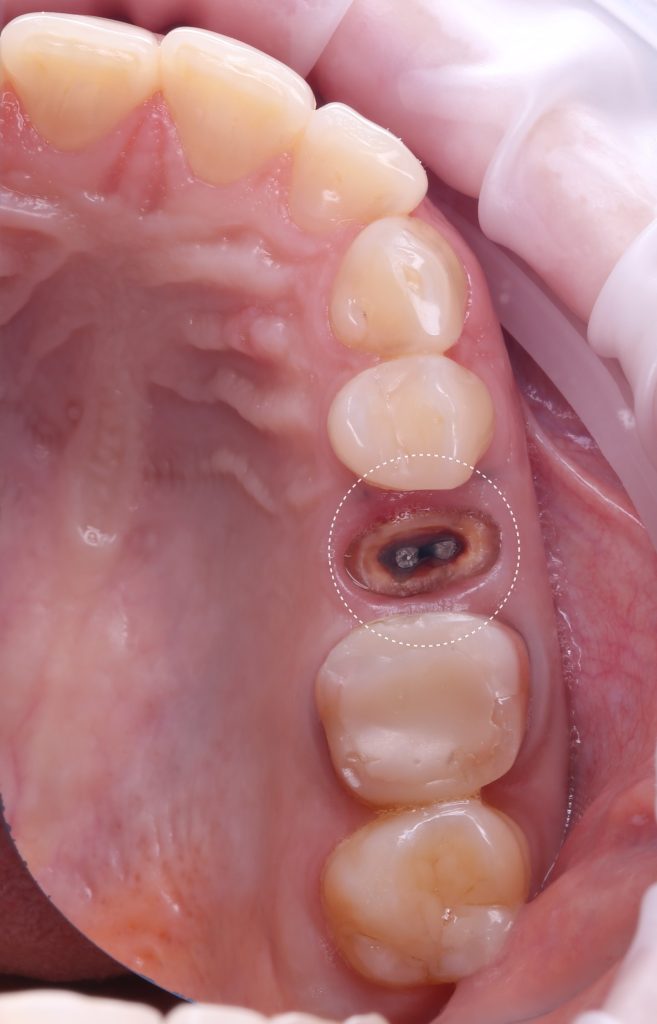

The patient came with complaints that his dental crown on tooth 25 (Universal 13) fell out

In order to predict the prognosis of the tooth, data from the Diagnocat radiological report and visualization capabilities of the 3D-Viewer tool were utilized, in addition to a clinical examination